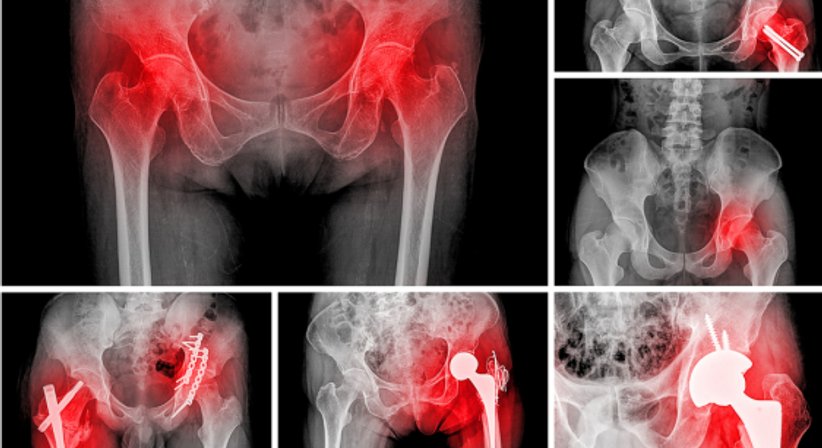

Eine Hüftprothese ersetzt ein geschädigtes Hüftgelenk. Neben Knieprothesen zählen Hüftprothesen zu den am häufigsten implantierten Prothesen im Bereich der orthopädischen Chirurgie, die häufigste Indikation für den Ersatz des Hüftgelenks ist die fortgeschrittene Hüftarthrose (Coxarthrose).

Nach dem Kniegelenk ist das Hüftgelenk das zweitgrößte Gelenk des menschlichen Körpers. Das Gelenk bildet den beweglichen Übergang zwischen dem Becken und dem Oberschenkelknochen. Schmerzen und Bewegungseinschränkungen im Bereich der Hüfte können auf verschiedene Ursachen zurückzuführen sein; ist das Hüftgelenk durch degenerative Veränderungen, Verletzungen oder Erkrankungen stark geschädigt bzw. verschlissen und helfen konservative und gelenkerhaltende Behandlungen (z.B. Physiotherapie, schmerz- und entzündungshemmende Medikamente) nicht mehr ausreichend, um die Schmerzen zu mildern und die Beweglichkeit und Funktionalität des Hüftgelenks in ausreichendem Maß wiederherzustellen, dann sollte über eine Hüftprothese ("künstliche Hüfte") nachgedacht werden, mithilfe welcher die Lebensqualität dauerhaft wiederherstellt werden kann.

Es stehen unterschiedliche Prothesen und Operationstechniken zur Verfügung, um das körpereigene Gelenk zu ersetzen. Der Eingriff kann minimal-invasiv oder offen erfolgen. Die minimal-invasive Methode bietet Patienten einige Vorteile, allen voran, dass die Muskulatur seitlich der Hüfte bei der Operation nicht durchtrennt wird. Dadurch werden Vernarbungen und Heilungsschmerzen an diesen für die Fortbewegung wichtigen Muskeln vermieden, was im Regelfall eine kürzere Rehabilitationszeit bedeutet. Patienten sind nach der Operation schneller wieder selbstständig mobil und können alltäglichen und sportlichen Aktivitäten wieder früher nachgehen. Welche Prothese und Operationstechnik im Einzelfall am besten geeignet sind hängt von der Ausgangssituation des Patienten und individuellen Faktoren ab. Sind die Voraussetzungen gegeben, dann führe ich Hüftimplantationen bei Möglichkeit minimal-invasiv durch.

Der genaue Ablauf des Eingriffs und alle wichtigen Punkte (richtiger Zeitpunkt für die Operation, Wahl der Prothese, Verankerungsart, um die Prothese mit den Knochen der Hüfte zu verbinden etc.) werden nach Vorliegen einer exakten Diagnose eingehend besprochen und an die spezifischen Bedürfnisse und Anforderungen des Patienten angepasst.